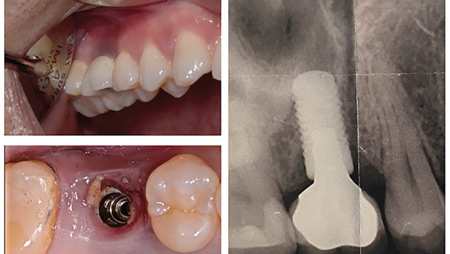

Key Factors in Maintenance Protocols for Dental Implant Restorations – A Scoping Review

Gebril-FIG-1-thumbnail alternate text for this image

Statement of Problem It has been established that maintenance is of utmost importance in the delivery of comprehensive prosthodontic treatment. Therefore, consideration of the possible factors which impact the maintenance phase is essential to take into account during the treatment planning stage. Although, most clinicians recognize the importance of prosthesis maintenance, few of them are … Read more